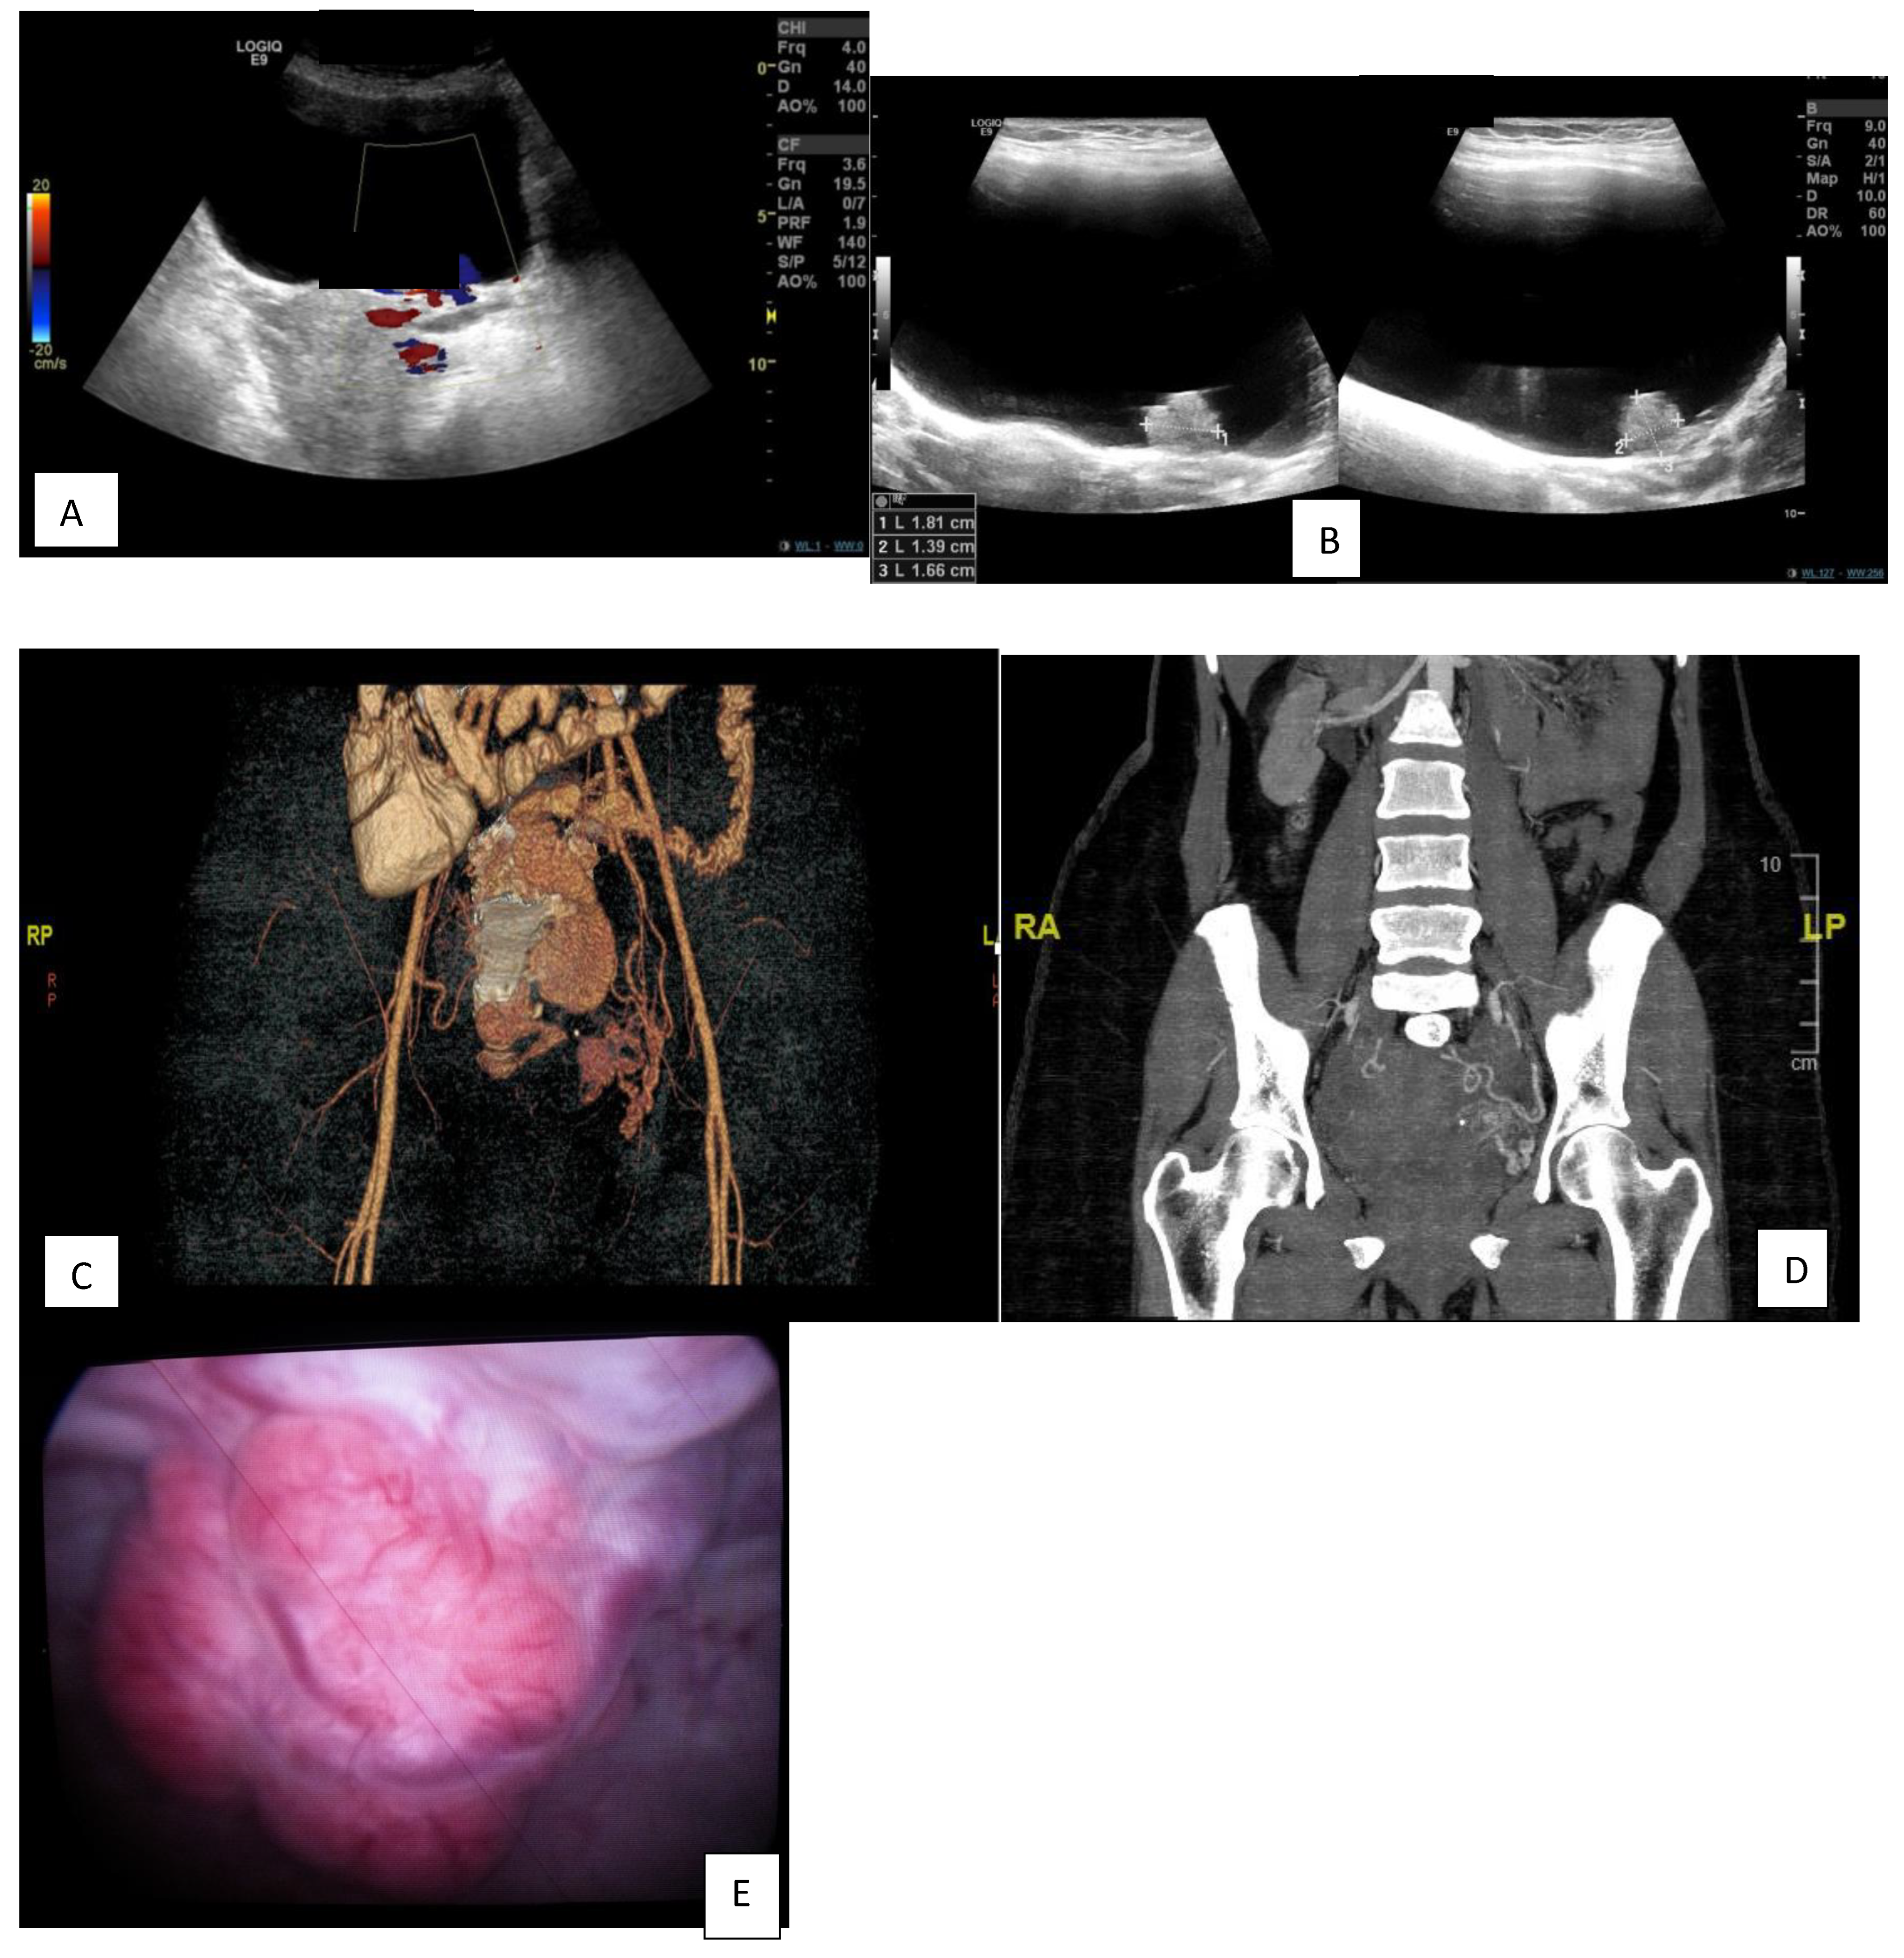

| Computed tomography with contrast medium | Showed a 17.1 × 24.2 mm polypoidal hyper-vascular lesion, as previously described, arising from the urinary bladder wall (and thus unlikely to be arising from the anterior wall of the uterus). |

| Cystoscopy | Showed a large, bluish-red, pulsatile, vascularized submucosal mass with large dilated submucosal vessels, a wide-based stalk and no active bleeding in the posterior wall of the urinary bladder, measuring about 2 × 3 cm, with urine cytology negative. |

| First angioembolization | Selective catheterization of the left internal iliac artery using a C2 angiocatheter followed by angioembolization of the left superior vesical arteries, approaching from the anterior division of the left internal iliac artery. |

| In 2018, recurrence after 5 years of follow-up | US showed a distended UB with a polypoidal soft tissue mass measuring 16 × 16 mm with internal vascularity, nidus in afferent and efferent vessels, and turbulence in the flow. |

| In 2018, second angioembolization | The patient underwent selective catheterization of the left internal iliac artery using a C2 angiocatheter; selective angiography revealed recanalization of the previously embolized left superior vesical arteries from the anterior division of the left internal iliac artery and supplying the known intra-resulting AVM. Selective catheterization of the left superior vesical artery using a 3F microcatheter, followed by embolization of the artery, was executed using ONYX. |